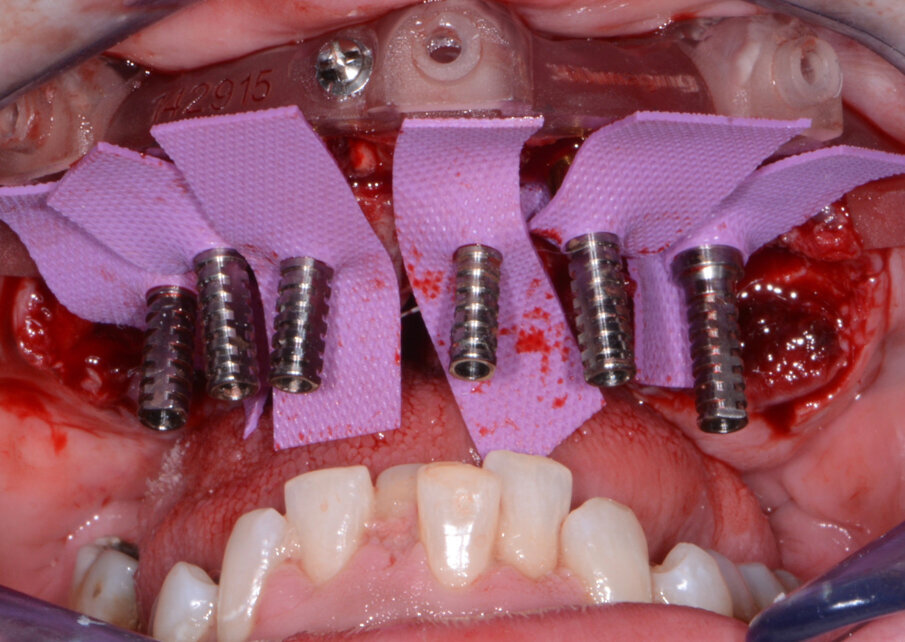

Fig. 11: Maxillary temporary cylinders isolated.

The maxillary provisional restoration was tried in to verify a passive fit over the temporary abutments. Once fit had been confirmed, trimmed dental dam pieces were placed to avoid the restoration (Fig. 11) from locking on during the relining procedure with REBASE III FAST set hard reline material (Tokuyama Dental). After the material had polymerised, the immediate provisional restoration was removed and any access material was removed with the Torque Plus laboratory handpiece (Aseptico) and an acrylic bur (Komet). The same procedures were accomplished in the mandibular arch (Figs. 12–14). Once trimmed and polished, the provisional restorations were seated and tightened with a torque wrench at 15 Ncm (Fig. 15). The access openings were filled in three-quarters of the way with Teflon tape, followed by Cavit filling material (3M ESPE). A postoperative panoramic radiograph was taken immediately after the surgery (Fig. 16).